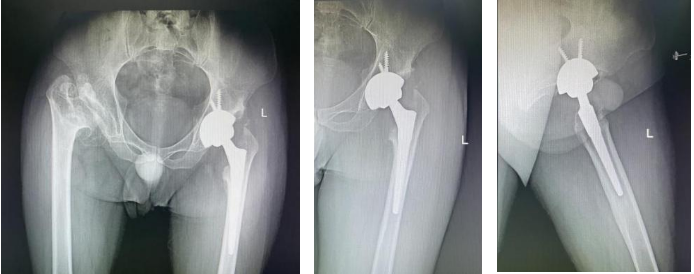

患者四年前出现双髋疼痛伴活动受限,症状渐进性加重,生活质量严重受影响。2025年5月,郝阳泉教授团队先对疼痛更剧的左侧髋关节实施全髋关节置换术,迅速解除患者左侧病痛,为后续治疗奠定基础。但由于患者右侧髋关节存在更严重的骨缺损与股骨头上移,导致双侧肢体长度差异显著,术后需通过左鞋垫高5厘米维持平衡,彻底解决双侧关节问题成为团队面临的核心挑战。

面对这一复杂病例,郝阳泉教授团队制定了科学的分期治疗策略,在首次手术与二次手术间隔期,精准指导患者进行科学代偿,既保障了患者过渡期的行走安全,更为二次手术的精准实施预留了最佳条件,体现了团队对复杂关节疾病的系统性诊疗思维与成熟临床经验。